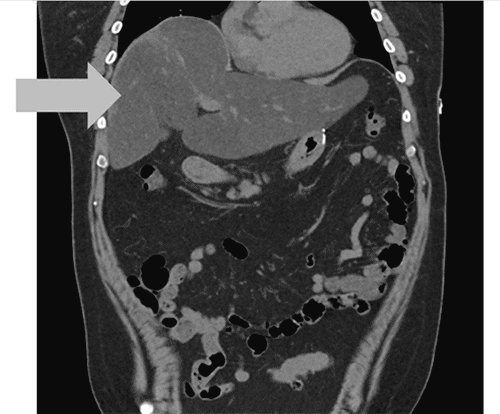

Figure 2. Abdominal CT Scan Demonstrating New-onset Hepatic Steatosis. Published with Permission

One year later, the patient had achieved significant weight loss (69.5%) and his post-splenectomy leukopenia resolved. However, he continued to experience abdominal pain, nausea, and reflux. Treatment with proton pump inhibitors and H2 blockers provided no relief. An upper gastrointestinal series and two EGDs showed no signs of reflux or leaks. EGDs revealed grade A esophagitis and chronic gastritis without evidence of sarcoidosis. Due to transaminitis, methotrexate was switched to Remicade, leading to temporary improvement in abdominal symptoms and transaminitis. However, he eventually became unresponsive to Remicade and presented to the emergency department multiple times with worsening abdominal pain, nausea, transaminitis (ALP 172, ALT 80, AST 174), and new-onset direct hyperbilirubinemia (total bilirubin 2.5, direct bilirubin 1.2). Imaging studies at this point revealed new findings of severe hepatic steatosis and mild hepatomegaly (Figure 3). A subsequent liver biopsy confirmed hepatic sarcoidosis with portal/pericellular fibrosis and severe steatosis (Figure 4). Azathioprine was initiated in place of Remicade, and the patient was referred to a tertiary center for liver transplant evaluation.

In our case report, our patient also developed splenic sarcoidosis with increasing splenomegaly and persistent leukopenia. This complication, while presenting in a reported range of 5.6% to 50% of sarcoidosis cases,5,8 often occurs alongside hepatic involvement, as seen in this case. While hepatic sarcoidosis is itself frequent (50% to 90% of patients), it frequently presents without lab abnormalities (less than a third of cases).9,10 Typically, hepatic sarcoidosis can manifest with transaminitis in a cholestatic pattern, less commonly progressing to portal hypertension and, rarer still, hepatic failure requiring liver transplantation.10,11 In this case, the initial transaminitis was attributed to methotrexate, but the development of severe steatosis and hepatomegaly after discontinuation suggests an alternative explanation, potentially related to the underlying sarcoidosis.